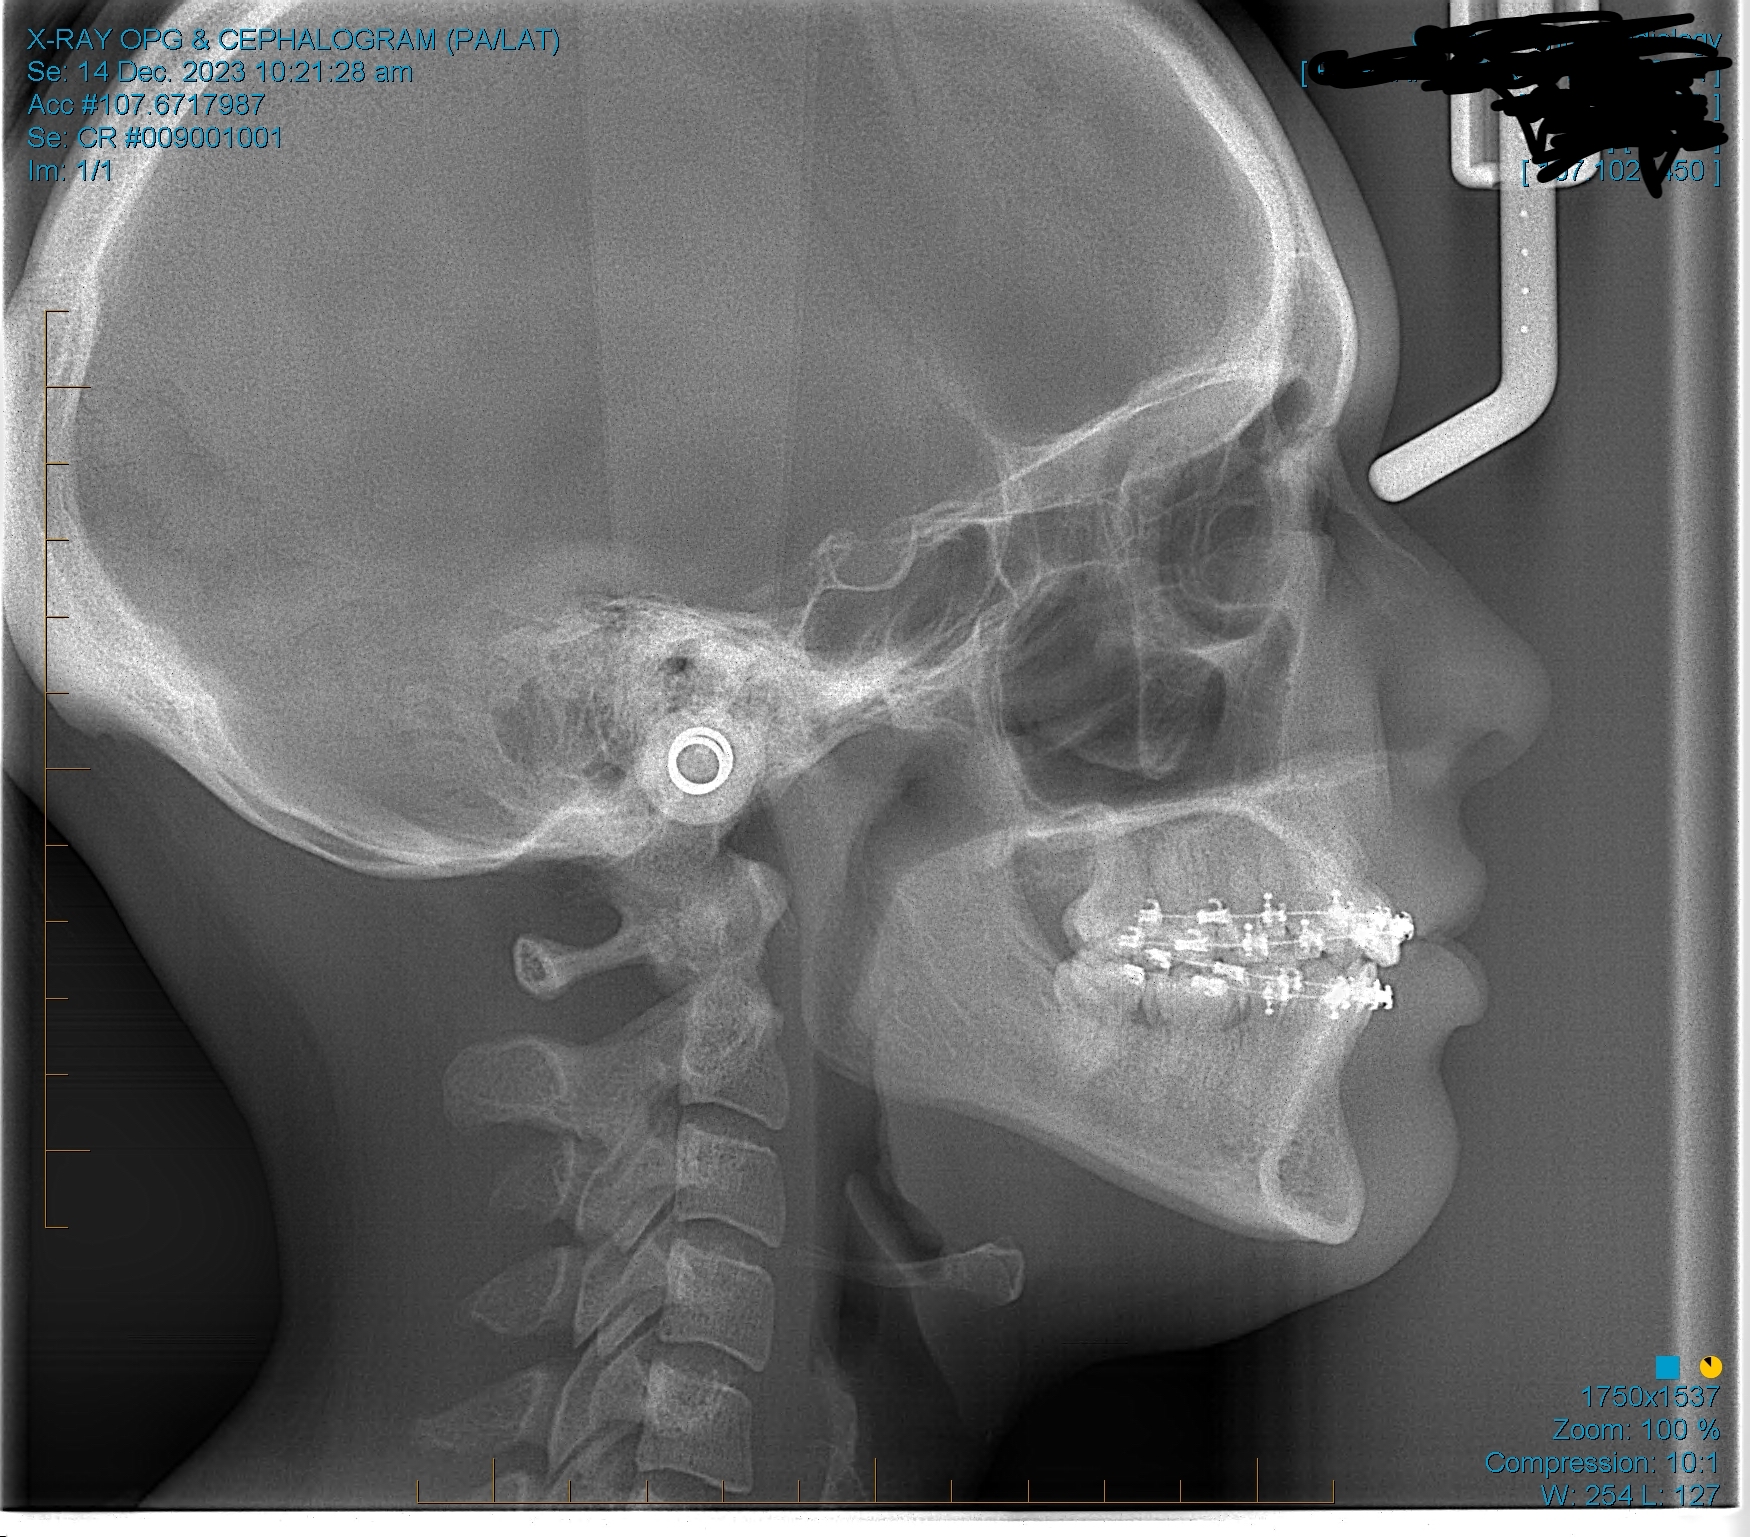

sfs, no ramus and zygos, retrusive, low hyoid, crossbite, crooked/slanted and retracted maxilla, mandible asymmetry, right side of face grown more than left, 8 extractions at 13 (including premolars).